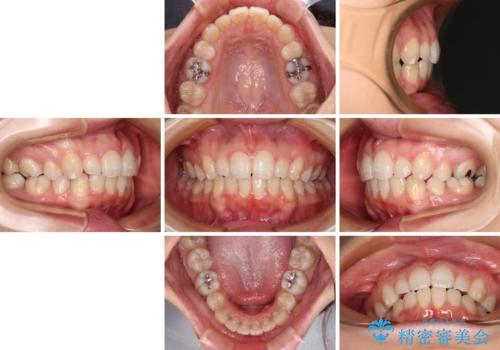

- 30代女性

- インビザライン・ライト

- 下顎前歯を中心に、以前行った矯正治療の後戻りが気になるとのことで来院された患者様です。

後戻りは軽度であったため、インビザライン・ライトにて治療を行うこととしました。

治療途中で出産をされたため、通院が困難となりましたが、インビザライン・ライトでの治療可能期限である2年以内に無事に治療を終えることができました。